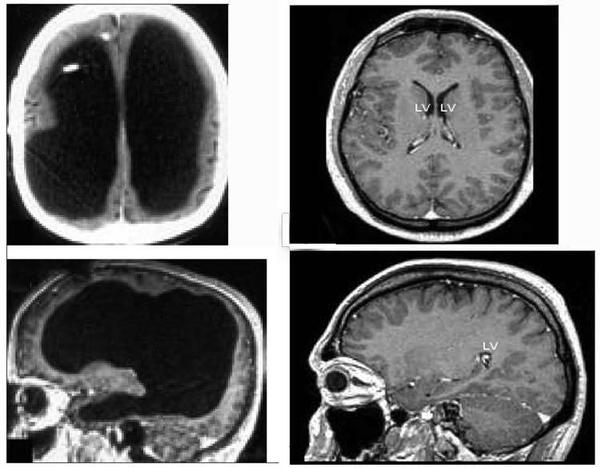

Пациентка Ж, 20 лет. Направлена неврологом по месту жительства.

Предъявляла жалобы на головные боли гипертензионного характера, периодическое онемение левой половины лица, левой руки и ноги, снижение памяти.

Ухудшение состояния в течение последних 2 месяцев. Консервативное лечение без эффекта. При обследовании по данным МРТ головного мозга выявлена окклюзионная тривентрикулярная гидроцефалия. Стеноз водопровода мозга.

В данном случае методом выбора явилась эндоскопическая вентрикулоцистерностомия дна III желудочка с целью создания обходной ликвороциркуляции.

В послеоперационном периоде наблюдается положительная динамика. Пациентка отметила регресс головных болей, улучшение когнитивных функций.